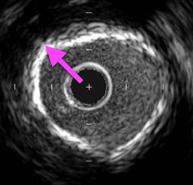

石灰化病変のIVUS画像は、プラーク部分に白い壁があり、壁の外側が黒く抜けているのが特徴だ!

石灰化病変はプラークにカルシウムが沈着しており、骨のように固くなっている。

そのため、安易にステントを留置するとステントが拡張不良を起す可能性が高いぞ!

ステントの拡張不良を防ぐには前拡張をしっかり行い、十分に病変を広げた後にステントを留置する必要がある。

石灰化病変の前拡張にはカッティングバルーンが有効だ。

また、必要に応じてロータブレーターを使用することもあるぞ!

いずれにせよ、石灰化病変攻略の鍵は入念な前拡張だ。

ステントを拡張不良させないため、しっかり行おう!